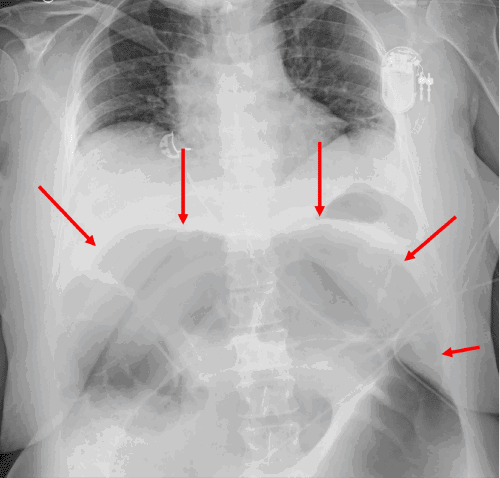

Upon initial physical examination in the ED, her blood pressure was 130/89 mmHg, pulse rate was 94 beats/minute, and temperature was 36.9°C. The abdominal examination was notable for a rotund, markedly distended, tympanic, and firm abdomen. Laboratory investigations revealed a normal hemoglobin and platelet count, with a white blood cell (WBC) count of 7.2 × 10⁹/L (reference range: 3.4-9.6 × 10⁹/L). Significant hypokalemia was present, with a serum potassium level of 2.7 mmol/L (reference range: 3.6-5.2 mmol/L). Her serum lactate was 1.3 mmol/L (reference range: 0.5-2.2 mmol/L), while her ammonia level was elevated at 73 mcmol/L (reference range: <51 mcmol/L), and arterial pH was 7.42 (reference range: 7.32-7.43). An episode of hypoxemia, with oxygen saturation dropping to 88% on room air, necessitated the initiation of supplemental oxygen at 2 liters/minute via nasal cannula. An immediate chest X-ray revealed significant colonic distension (Figure 1). Subsequently, an abdominal computed tomography (CT) scan was obtained, which demonstrated a large bowel volvulus localized to the region of the splenic flexure, with marked distension of the proximal large bowel up to 11 cm in diameter (Figure 2). A urinalysis was positive for a urinary tract infection, and intravenous ceftriaxone was initiated.

Figure 2. CT Confirming Splenic Flexure Volvulus. Published with Permission

(A) Axial and (B) Coronal views from a contrast-enhanced CT scan of the abdomen and pelvis. Note  massive distension of the transverse and descending colon, with a characteristic "whirl sign" or abrupt transition point at the splenic flexure, confirming splenic flexure volvulus